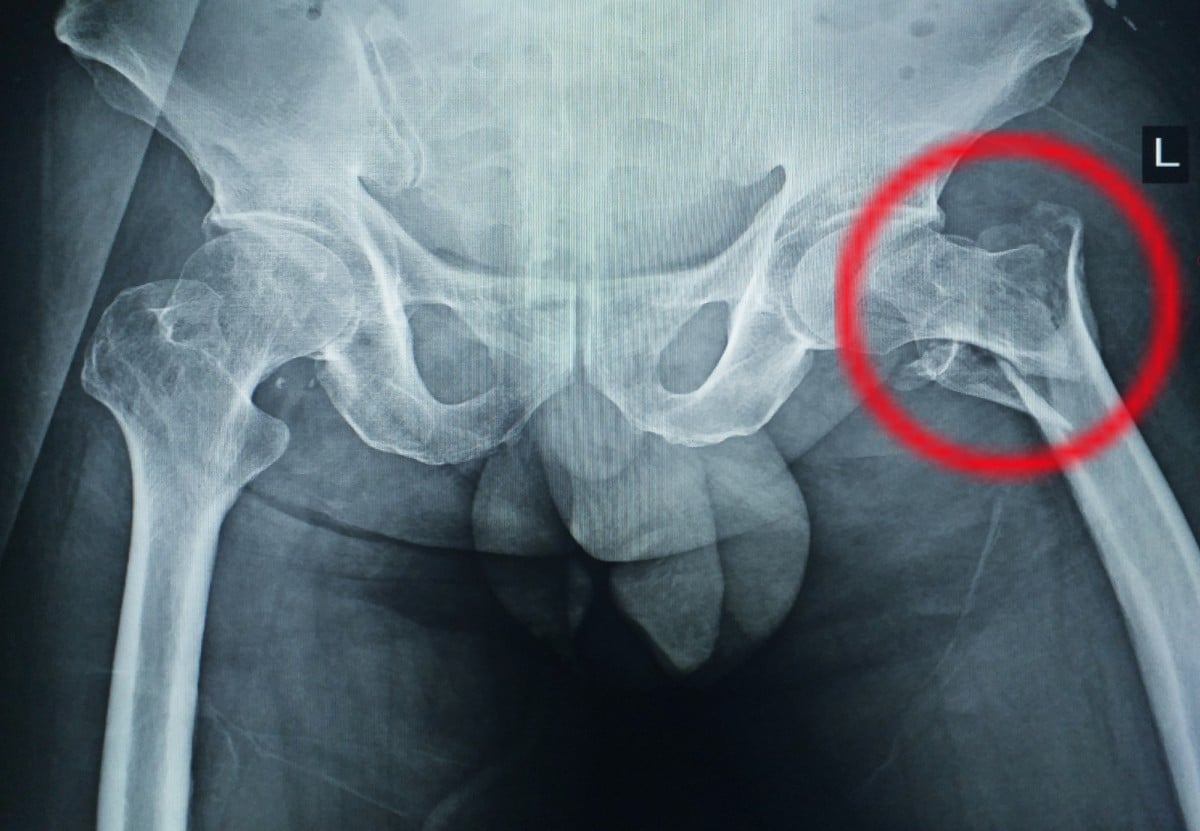

Hip Fracture

A hip fracture refers to a break in the upper portion of the femur (thigh bone). It occurs most often in the elderly, especially after a fall from standing height. In younger people, hip fractures can be caused by severe impact, such as a car accident or fall from a ladder. Hip fractures are painful injuries that will require surgical treatment in order to restore motion and reduce pain.

When the hip is fractured, there will be severe pain in the hip or groin, as well as bruising and swelling in the affected area. You may be unable to put weight on the leg on the side affected by the fractured hip. In more serious cases, you may even be unable to walk or to get back up after a fall. Other signs of fractured hip are leg length discrepancy or the outward turning of the leg on the side of the injured hip.